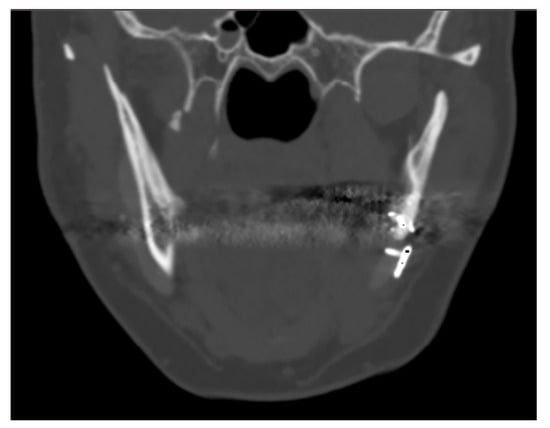

3.2. Maxillo-Facial Surgery

Postoperative CT scans of 11 patients were studied. In 11 out of 12 CT scans, it was possible to note radiological evidence of bone regrowth on the surface and edges of the implant; in those implants where factory-created holes were present, bone regrowth was also noted in them.

The one case in which bone regrowth was not noticeable is a female patient where complex mandibular implants were designed with a very small bone/implant interface. No signs of bone resorption were noted at the bone/implant interface.

The case of maxillofacial surgery where bone regrowth was not observable underscores the importance of a sufficient bone–prosthesis interface for a successful osteointegration (see Figure 3). The neurosurgical case series, in which the interface between bone and prosthesis for cranioplasty is minimal, further corroborated this statement. Studies have shown that a larger contact area between the implant and bone facilitates osteoblastic activity and bone ingrowth [47]. In addition, implants with roughened surfaces or porous coatings promote greater bone ingrowth compared to smooth-surfaced implants [48,49]. For this reason, factory-created holes are a valuable aid in the creation of bone tissue within them, as demonstrated in the previously analyzed case. Other studies aimed at enhancing the bioactivity of PEEK to improve the bone–implant interface are still in the in vitro stage, but we anticipate significant progress soon [50,51].

Figure 3.

The maxillo-facial surgery case representing the absence of ossification, caused by poor interface between bone and prosthesis.